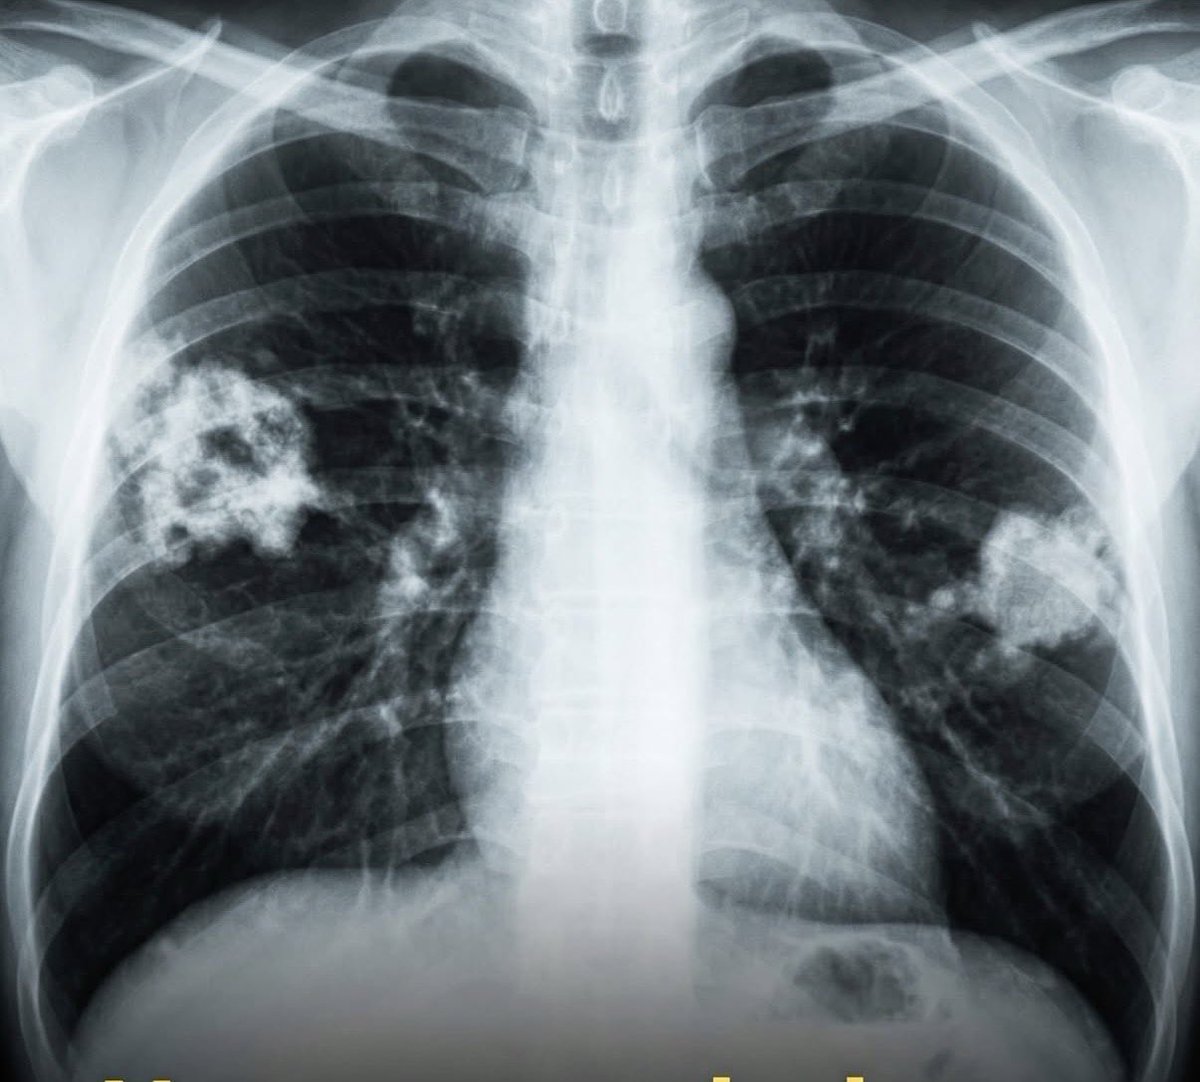

Li vedete quei segni bianchi nei polmoni? Sono gli effetti delle sigarette elettroniche. Ormai è noto a livello medico, e non solo. Le sigarette elettroniche aromatizzate causano danni polmonari permanenti. Negli Stati Uniti, molti adolescenti hanno sviluppato una patologia chiamata “polmone a popcorn” dopo aver svapato per vari anni. È una condizione che ti cambia la vita e, soprattutto, non ha una cura. Il nome medico è la bronchiolite obliterante, una patologia che danneggia le vie aeree più piccole dei polmoni, causando tosse cronica, respiro sibilante, estrema stanchezza e costante difficolta’ a respirare. Un tempo, il “polmone a popcorn” era collegato all’esposizione degli operai al diacetile negli impianti di produzione di popcorn per microonde. Ma oggi la preoccupazione si è spostata sulle sigarette elettroniche. Il vapore delle sigarette elettroniche contiene una complessa miscela di sostanze chimiche. Molti aromi sono sicuri da mangiare, ma quando vengono riscaldati e inalati, diventano pericolosi. Danneggiano direttamente il tessuto polmonare ed entrano nel sangue senza alcun filtro. Le svapo sono diventate particolarmente popolari tra gli adolescenti, soprattutto per i gusti dolci e fruttati. Ed è qui che il rischio aumenta. Più di 180 agenti aromatizzanti vengono utilizzati negli e-liquidi. Se riscaldate, possono formare composti tossici. Sebbene il diacetile sia stato rimosso da alcuni prodotti, sostituti come l’acetoina, anche questi potrebbero essere altrettanto dannosi. Quando queste sostanze chimiche vengono svapate, raggiungono i polmoni e altri organi in pochi secondi. Gli studi dimostrano che i giovani che svapano segnalano più problemi respiratori, anche rispetto ai fumatori. Ci vogliono normative più severe, etichette più chiare, test migliori e educazione sanitaria. Svapare può sembrare più sicuro che fumare. Ma l’inalazione di queste miscele chimiche può causare danni permanenti e ridurre l’aspettativa di vita. Il messaggio che svapare o fumare la sigaretta elettronica non fa male, e’ sbagliato!! Fanno male eccome!!